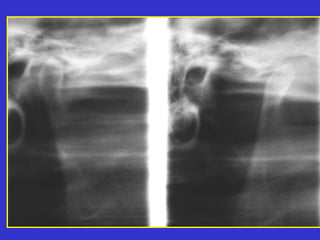

Este documento describe las diferentes proyecciones radiográficas utilizadas para examinar los senos paranasales, incluyendo las proyecciones básicas de Caldwell, Waters lateral y las proyecciones especiales como Hirtz y Waters mentonasal. También describe las diferentes estructuras anatómicas que componen el complejo ostiomeatal anterior y posterior de los senos paranasales.